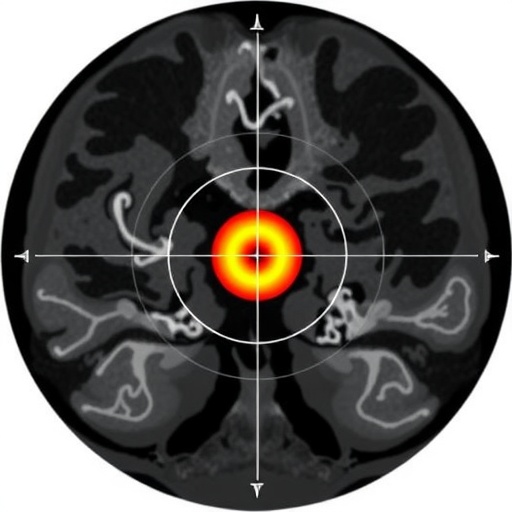

Vestibular schwannomas, benign tumors located at the vestibulocochlear nerve, present a unique treatment challenge due to their often irregular and complex three-dimensional configurations. Traditional Gamma Knife planning systems, such as GammaPlan, typically require numerous isocenters to conform radiation dose precisely around these irregular shapes. However, the computational and clinical burden of managing excessive isocenters raises concerns about planning efficiency and treatment safety. This study’s principal aim was to dissect and quantify the factors behind this phenomenon, offering an evidence-based perspective on tumor morphology’s role in isocenter utilization.

The research team meticulously gathered treatment data from 280 consecutive patients diagnosed with vestibular schwannoma who underwent Gamma Knife radiosurgery throughout 2023. Each patient’s treatment plan, designed using the sophisticated GammaPlan system, served as a rich dataset for evaluating morphological irregularity. Central to this analysis were three distinct metrics: standard sphericity (SS), volume ratio sphericity (VRS), and the coefficient of variance of diameters (DCV). These parameters illuminated varying dimensions of tumor shape complexity, from gross geometric conformity to volumetric proportion and diameter variability.

The research implications extend beyond mere morphological description; incorporating these quantitative irregularity measures into the Gamma Knife planning paradigm could revolutionize future treatment strategies. By predicting the complexity of isocenter deployment based on tumor shape metrics, clinicians and planners can better anticipate planning challenges, optimize isocenter allocation, and reduce overall treatment time. This not only enhances plan quality but also improves patient throughput and comfort, especially for intricate vestibular schwannoma cases.